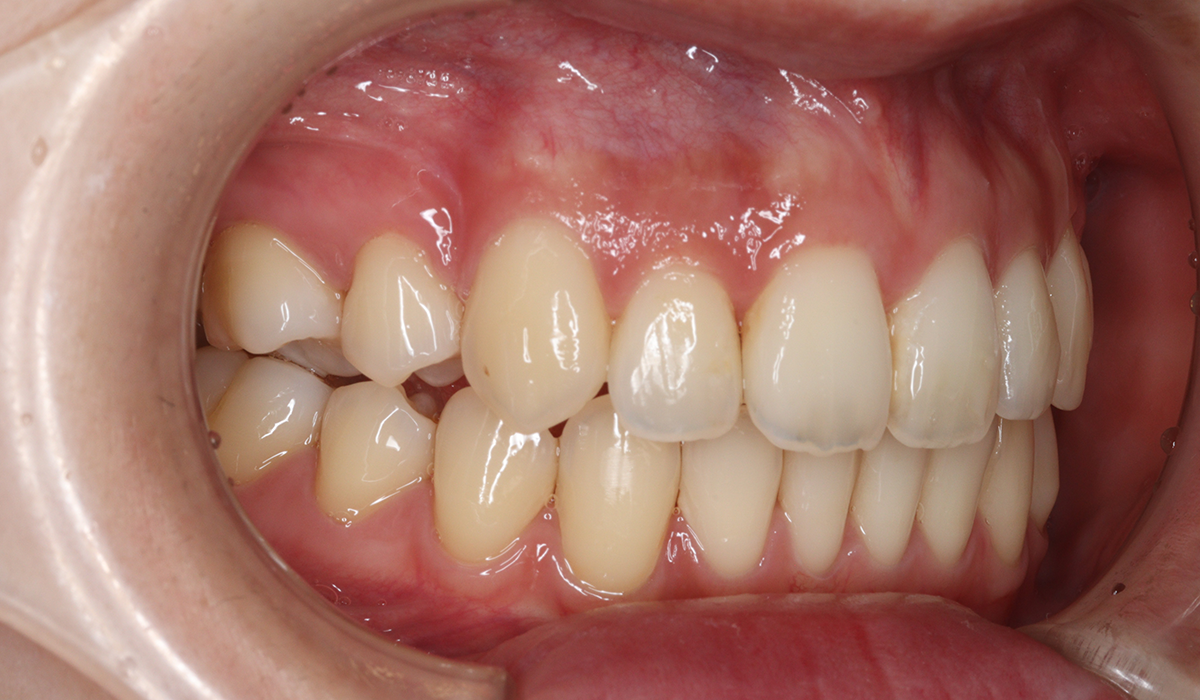

右側

術前